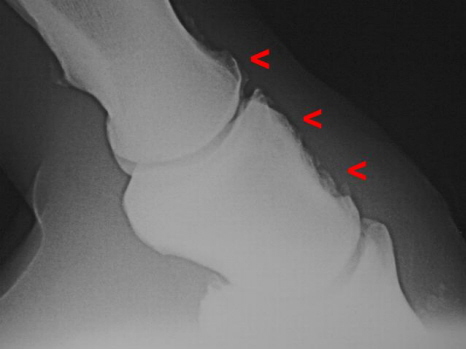

Arthrose Krongelenk, Kronbeinschale